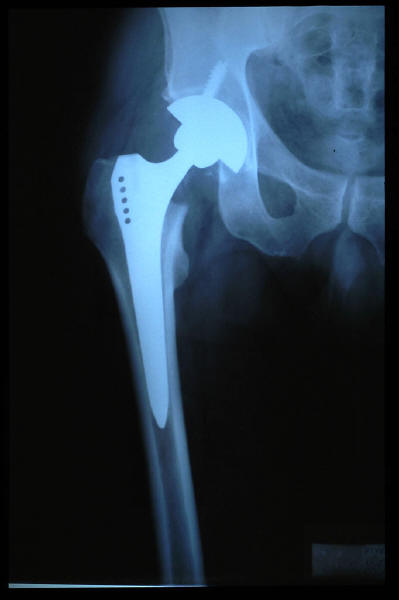

Fractura cuello fémur. Prótesis completa.

Fractura de fémur, prótesis parcial de cadera

Prótesis parcial de cadera

Prótesis de cadera.